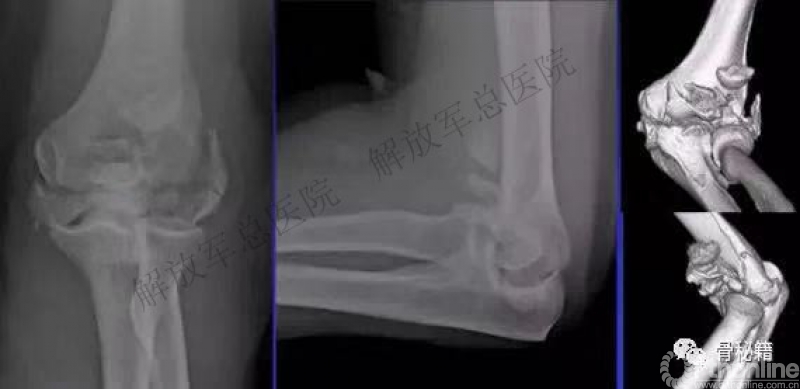

一、详细的术前评估

X线、CT、神经检查、等等。